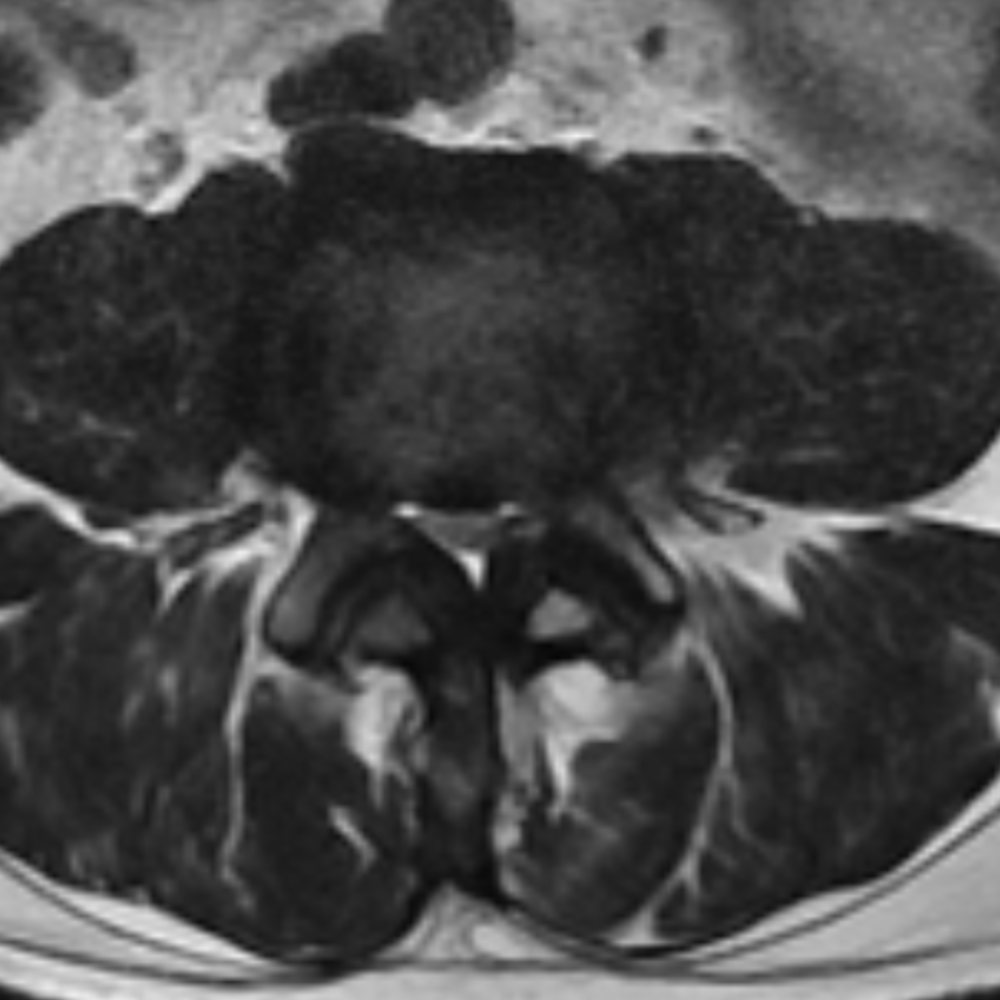

METRx – Minimally Invasive Lumbar Discectomy

The METRx Microdiscectomy system is a minimally invasive technique for treating lumbar disc herniation and relieving sciatica symptoms. It offers reduced muscle damage, smaller incisions, shorter hospital stays, and faster recovery, making it a significant advancement in spinal surgery.